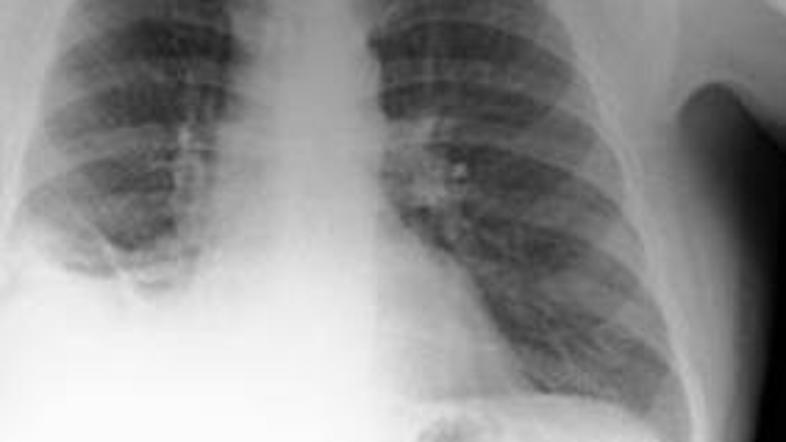

Rentgenska preiskava je pokazala na veliko senco v pljučih.

Rentgenska preiskava je pokazala na veliko senco v pljučih, po temeljitem pregledu pa so zdravniki ugotovili, da ima moški v pljučih stožec. Šlo je pravzaprav za igračo oziroma prometni stožec iz kompleta igrač znanega proizvajalca igrač Playmobil. Moški se je pozneje spomnil, da je to igračo dobil kot darilo za svoj sedmi rojstni dan.